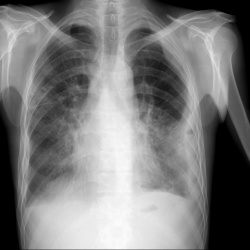

Здравствуйте, женщина 88 лет, жалобы на ухудшение самочувствия, гемоглобин 59. Лёгкие в пределах нормы?